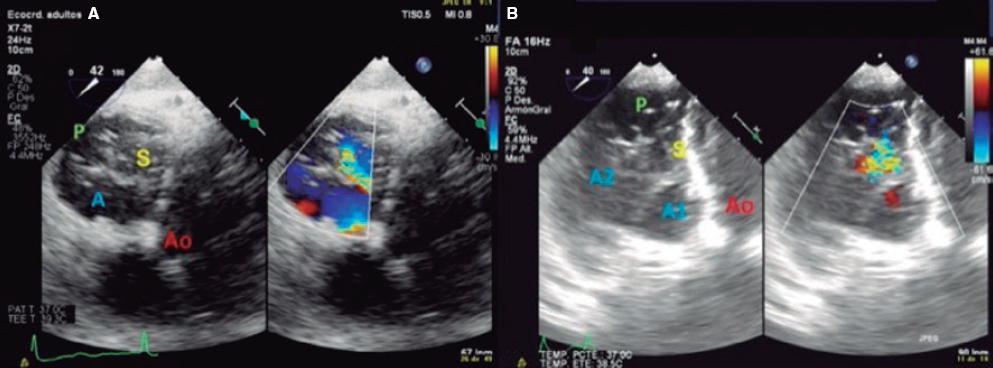

4. Transgastric view. These views are acquired by advancing the transducer towards the stomach. Starting at the baseline transgastric short axis and by rotating the transducer between 20° and 40° and making small clockwise rotations with anteversion, the optimal view to see the 3 tricuspid leaflets is acquired (TV short axis). This is the only 2D (bidimensional) view to see the 3 cusps and commissures simultaneously with the posterior leaflet in the nearby field, the anterior leaflet in the distant field, and the septal one adjacent to the septum (figure 3 and video 2 of the supplementary data). Images need to be optimized to make sure we are positioned on the tip of the leaflets and parallel to the valvular view. To do this we can start with a 2-chamber transgastric view of the RV at around 90º-110°. By using the X-plane tool to place the cursor on the tip of the leaflets, the orthogonal view will be acquired (that will be the TV short axis). This view provides a great deal of information on the TV:

Figure 3. Transgastric view. A: transgastric short axis view of a tricuspid valve with 3 cusps. B: transgastric short axis view of an anatomical variant with 2 scallops in the anterior leaflet. A: anterior; A1, scallop 1 of the anterior leaflet; A2, scallop 1 of the anterior leaflet; Ao, aorta; P, posterior; S, septal.

– Number of leaflets: there are usually 3, but we may find valves with several scallops and even 4 cusps in up to 40% of the patients.11

– Portion of the valve occupying each leaflet: it is very useful to make a graphic representation of what part of the circumference occupies each leaflet.

– Location of the regurgitant jet origin: the leaflets distal edge needs to be approached for a correct visualization of the coaptation defect in the short axis.